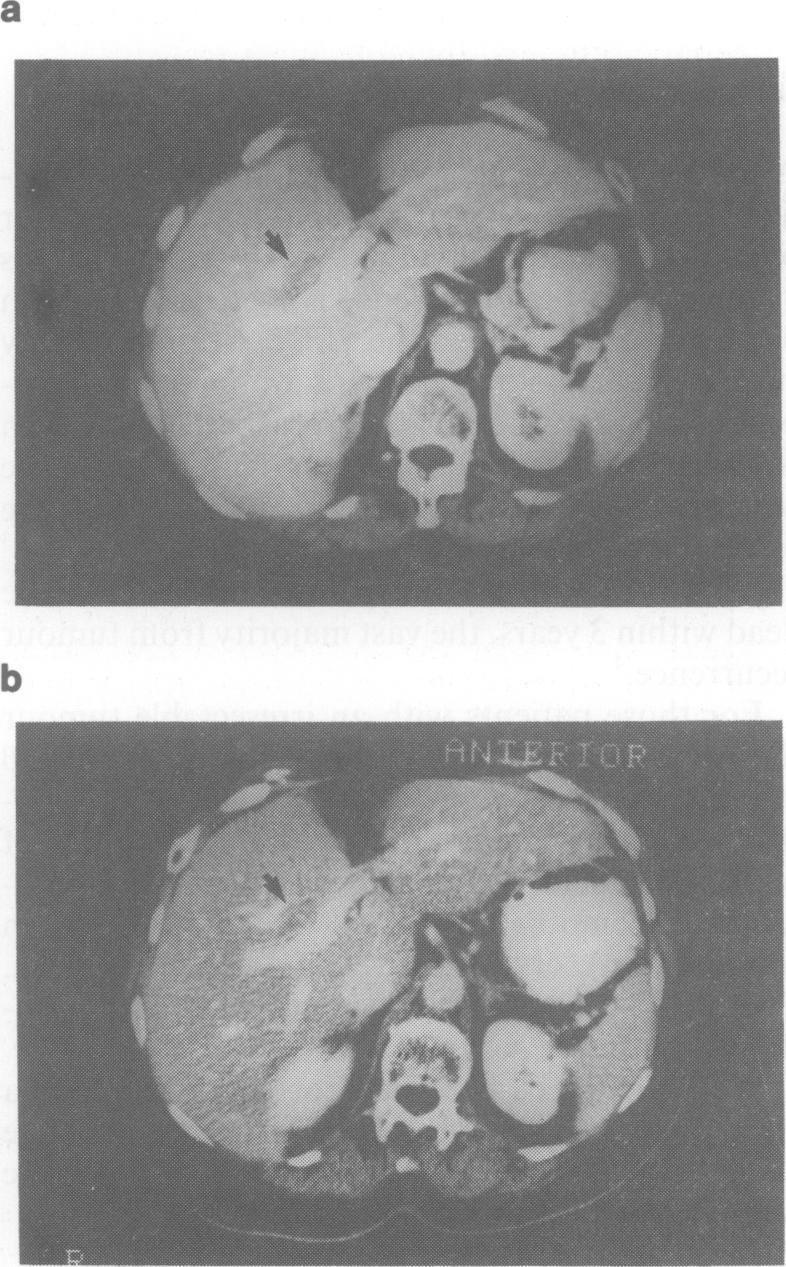

A case of recurrent hepatocellular carcinoma following resection is reported. The patient received 2 treatments of 131I-lipiodol administered via the hepatic artery at angiography. Good localization in tumour tissue was observed on subsequent computed tomographic scans and no adverse effects were seen after either treatment. After the first treatment 2 nodules of recurrent tumour were resected and proved to be totally necrotic. The patient remains well 9 months later with a persistently elevated serum alphafetoprotein but no evidence of residual tumour. It is suggested that 131I-lipiodol may be the treatment of choice for small tumours in elderly high-risk patients.

本文报告了1例肝癌切除术后复发的病例。该患者在血管造影时经肝动脉接受了2次131I-碘油治疗。在随后的计算机断层扫描中观察到肿瘤组织有良好的定位,且每次治疗后均未出现不良反应。第一次治疗后,切除了2个复发性肿瘤结节,病理证实完全坏死。9个月后患者情况良好,血清甲胎蛋白持续升高,但无残留肿瘤迹象。提示131I-碘油可能是老年高危患者小肿瘤的首选治疗方法。